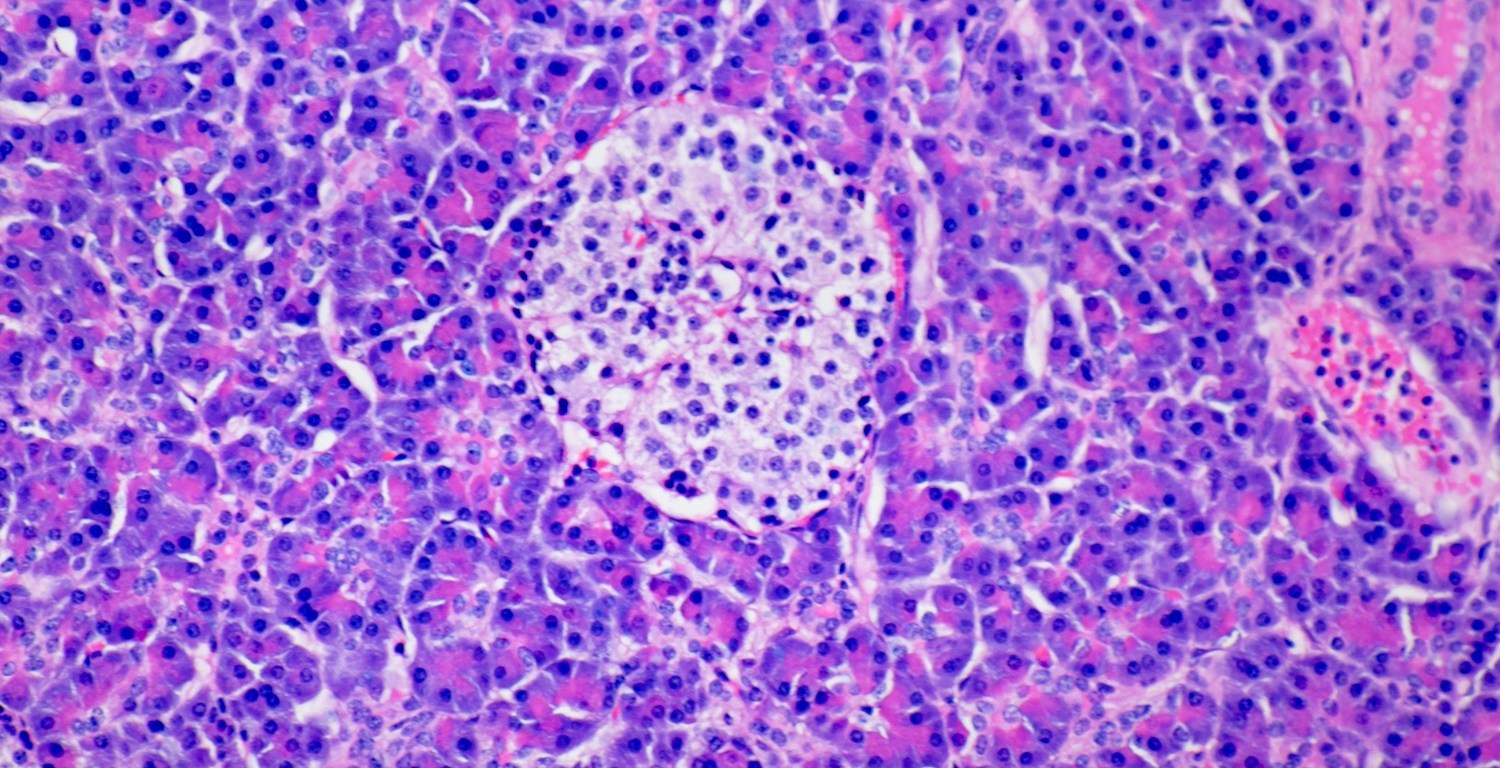

The pancreas is a retroperitoneal organ located behind the stomach. The organ is organized into lobes. The relationship between the pancreas and other organs can be viewed in the model here. Microscopically the organ has two parts – the endocrine part consists of the Islets of Langerhans, and the exocrine part consists of the acini.

The Islets of Langerhans are composed of three types of cells: Alpha, Beta, and Delta. These cells produce glucagon, insulin, and somatostatin, respectively. These are hormones that are released into the bloodstream.